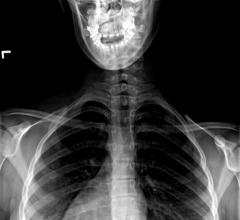

Shriners Hospitals for Children in Portland, Ore. announced the availability of the new EOS Imaging System, the first technology capable of providing full-body, 3-D images of patients in a natural standing or sitting position using low radiation doses.

November 9, 2011 – EOS Imaging announced that EOS installation has been completed at New York University Langone Medical Center, a world-class patient-centered integrated academic medical center. The clinical use of EOS is planned for early 2012. The full body, ultra-low dose 3-D orthopedic imaging system is already available in 10 North American medical centers to perform radiological examinations for the management and surgical planning of common orthopedic conditions such as scoliosis and joint disease.